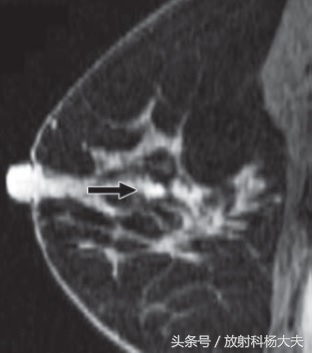

这个患者的MR做完后,在右侧乳腺内发现了异常的强化,但这种强化,按照BI-RADS分类来说,算是III级(IV级需要活检,V级是恶性)。

由于腋窝的淋巴结转移,只是高度怀疑乳腺来的转移瘤,而乳腺影像检查,B超和X线均为阴性,只有MR发现了异常强化,却仅仅是III级。

回了当地,经过与乳腺外科大夫协商,立刻手术,手术完整的切下了乳腺,病理科仔细的切片,找到了乳腺上那个小小的癌灶!